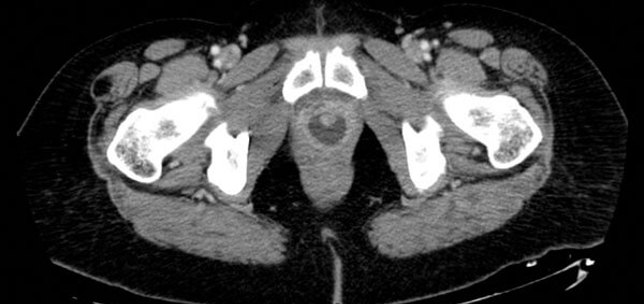

Functional / Reconstructive Urology , Infection

Urethral pathology

Infections and inflammation: Part 3

Infections and inflammation: Part 2